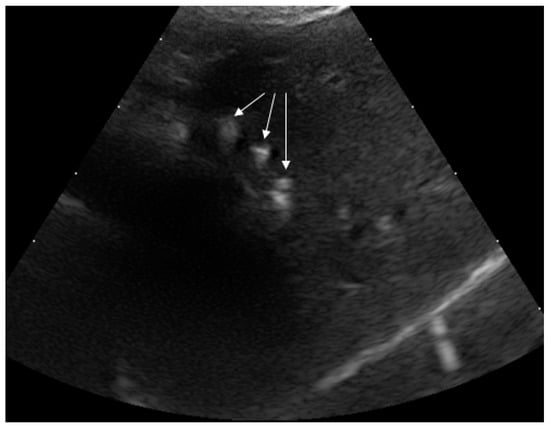

2.4.2. Ultrasound (US)